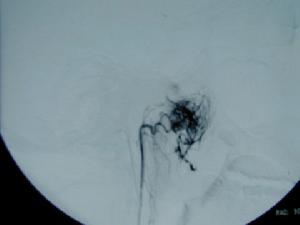

1、以手術治療為主,根據腫瘤大小多採用齶部切口進路,或經咽峽的無切口徑路將腫瘤切除。對巨大的腫瘤侵犯顱內時,可採用顱內、顱外聯合徑路進行手術。對於影響麻醉插管、或因腫瘤巨大、經口插管影響手術操作者,術前應作氣管切開術以保持呼吸道通暢。術前1d或手術日行同側頸外動脈結紮。術前應作好充分的輸液及輸血準備,分離摘除腫瘤時應儘量保持完整,可用冷凍法及降壓麻醉以減少出血,或行血管栓塞療法。

3、檢驗 血常規有無貧血,並查血型。X線攝片檢查,有條件應作CT掃描及數字減影血管造影。